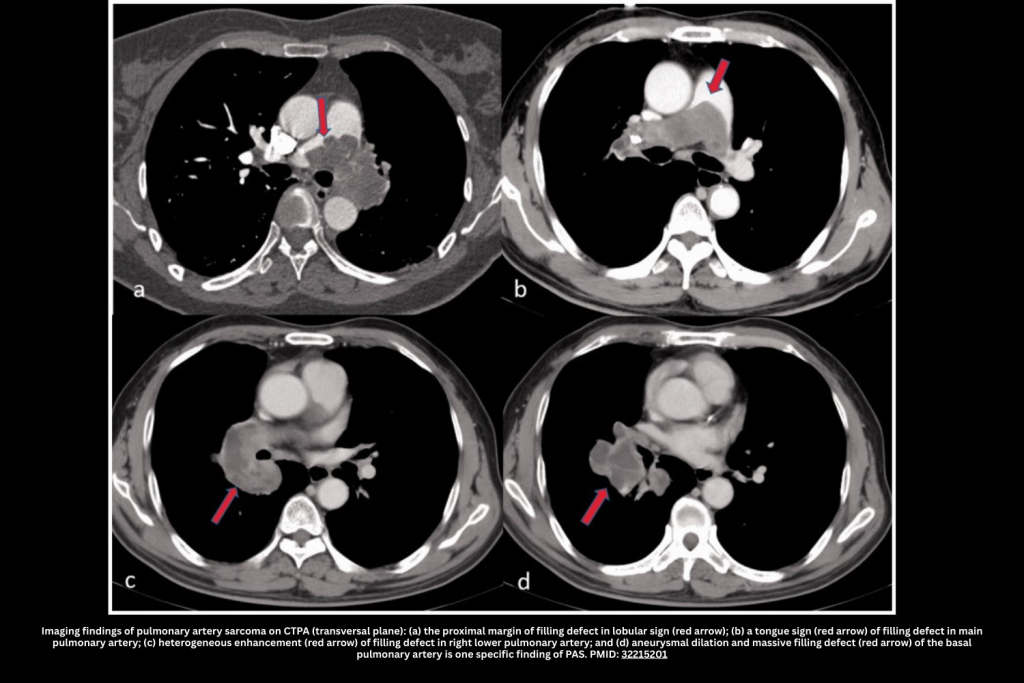

III. Pulmonary Artery Sarcoma (PAS)

Pulmonary artery sarcoma (PAS) is a rare but critical mimic of pulmonary embolism. Unlike embolic disease, it represents a primary malignant tumor of the pulmonary artery, most often diagnosed in middle age.

◾️Key Features (CTPA & Clinical Context):

- Epidemiology & Presentation

- Typically presents between 45–55 years; rare in patients <30.

- Gradual onset of pulmonary hypertension and RV failure over months.

- Symptoms are often mild compared to dramatic CT findings.

- Red flags: Constitutional symptoms (fever, weight loss, night sweats) and failure to improve with anticoagulation.

- 🩻Imaging Clues

- Most common findings:

- A Lobulated or nodular appearance is often seen.

- A single, central lesion tends to occur (unlike a pulmonary embolism, which frequently causes multiple, bilateral filling defects).

- Filling of the entire arterial lumen (“eclipsing vessel sign”).

- More specific features that may occasionally be seen:

- Vessel expansion due to mass effect.

- Invasion of the lung parenchyma or mediastinum.

- Hematogenous metastasis causes randomly distributed nodules in the lung parenchyma.

- Calcification may occur; if encountered, this suggests against PE (although calcification can also occur in the context of chronic thromboembolic pulmonary hypertension).

- Lesions may have low attenuation. Heterogeneous contrast enhancement may occur (although this won’t be captured on a CT angiogram).

- Diagnosis

- Consider when CT findings are disproportionate to symptoms or when “PE” does not resolve with treatment.

- MRI or PET can support diagnosis; tissue confirmation via endovascular biopsy or surgical resection.